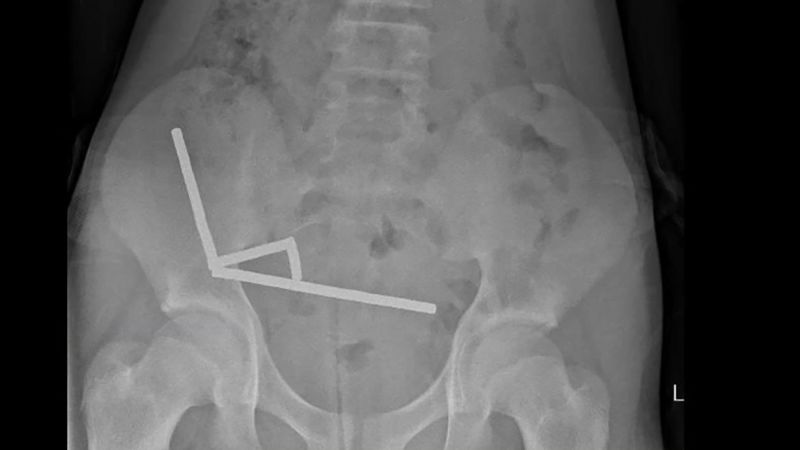

This undated handout released on Friday from the New Zealand Medical Journal (NZMJ) shows an x-ray image of pieces of high-power magnets clumped up in the intenstines of a New Zealand teenager in Tauranga. New Zealand Medical Journal/AFP/Getty Images

A 13-year-old boy in New Zealand was hospitalized after swallowing dozens of high-powered magnets, ultimately losing part of his bowel, according to a recent case report in the New Zealand Medical Journal .

The boy, whose identity was not disclosed, ate between 80 and 100 neodymium magnets, each five millimeters by two millimeters in size, according to the report.

The high-powered magnets, often sold as desk toys for adults, are small yet dangerous if swallowed. Their strong magnetic pull can cause parts of the digestive tract to stic